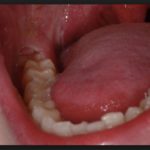

Ученые говорят, что за последние несколько тысячелетий челюсть человека стала уже на 10 сантиметров по сравнению с тем, как она выглядела у первобытных людей. Но количество зубов не изменилось, только теперь им остается все меньше места для нормального расположения. Поэтому, когда лезет зуб мудрости, болит все вокруг. Кажется, соседние резцы смещаются. Так происходит наряду с отеком, температурой и другими неприятными симптомами. Стоит ли их терпеть, либо можно просто пойти и удалить «восьмерки» – все зависит от процесса роста, симптомов.

Врачам до сих пор сложно точно определить, под воздействием каких факторов, а также во сколько лет лезут зубы мудрости у человека. Они могут не появиться вообще или прорезываться сразу все вместе. В отличие от коренных собратьев, их появление сопровождается неприятными симптомами. Боли возникают не из-за «восьмерок», а раздражения нервов в мягких основаниях. Моляры часто растут в разные стороны, упираясь в щеки или соседние «семерки», и болят именно они, а не прорезывающиеся их «сородичи». Дискомфорт сильнее ощущается внизу, потому что там кость более плотная.